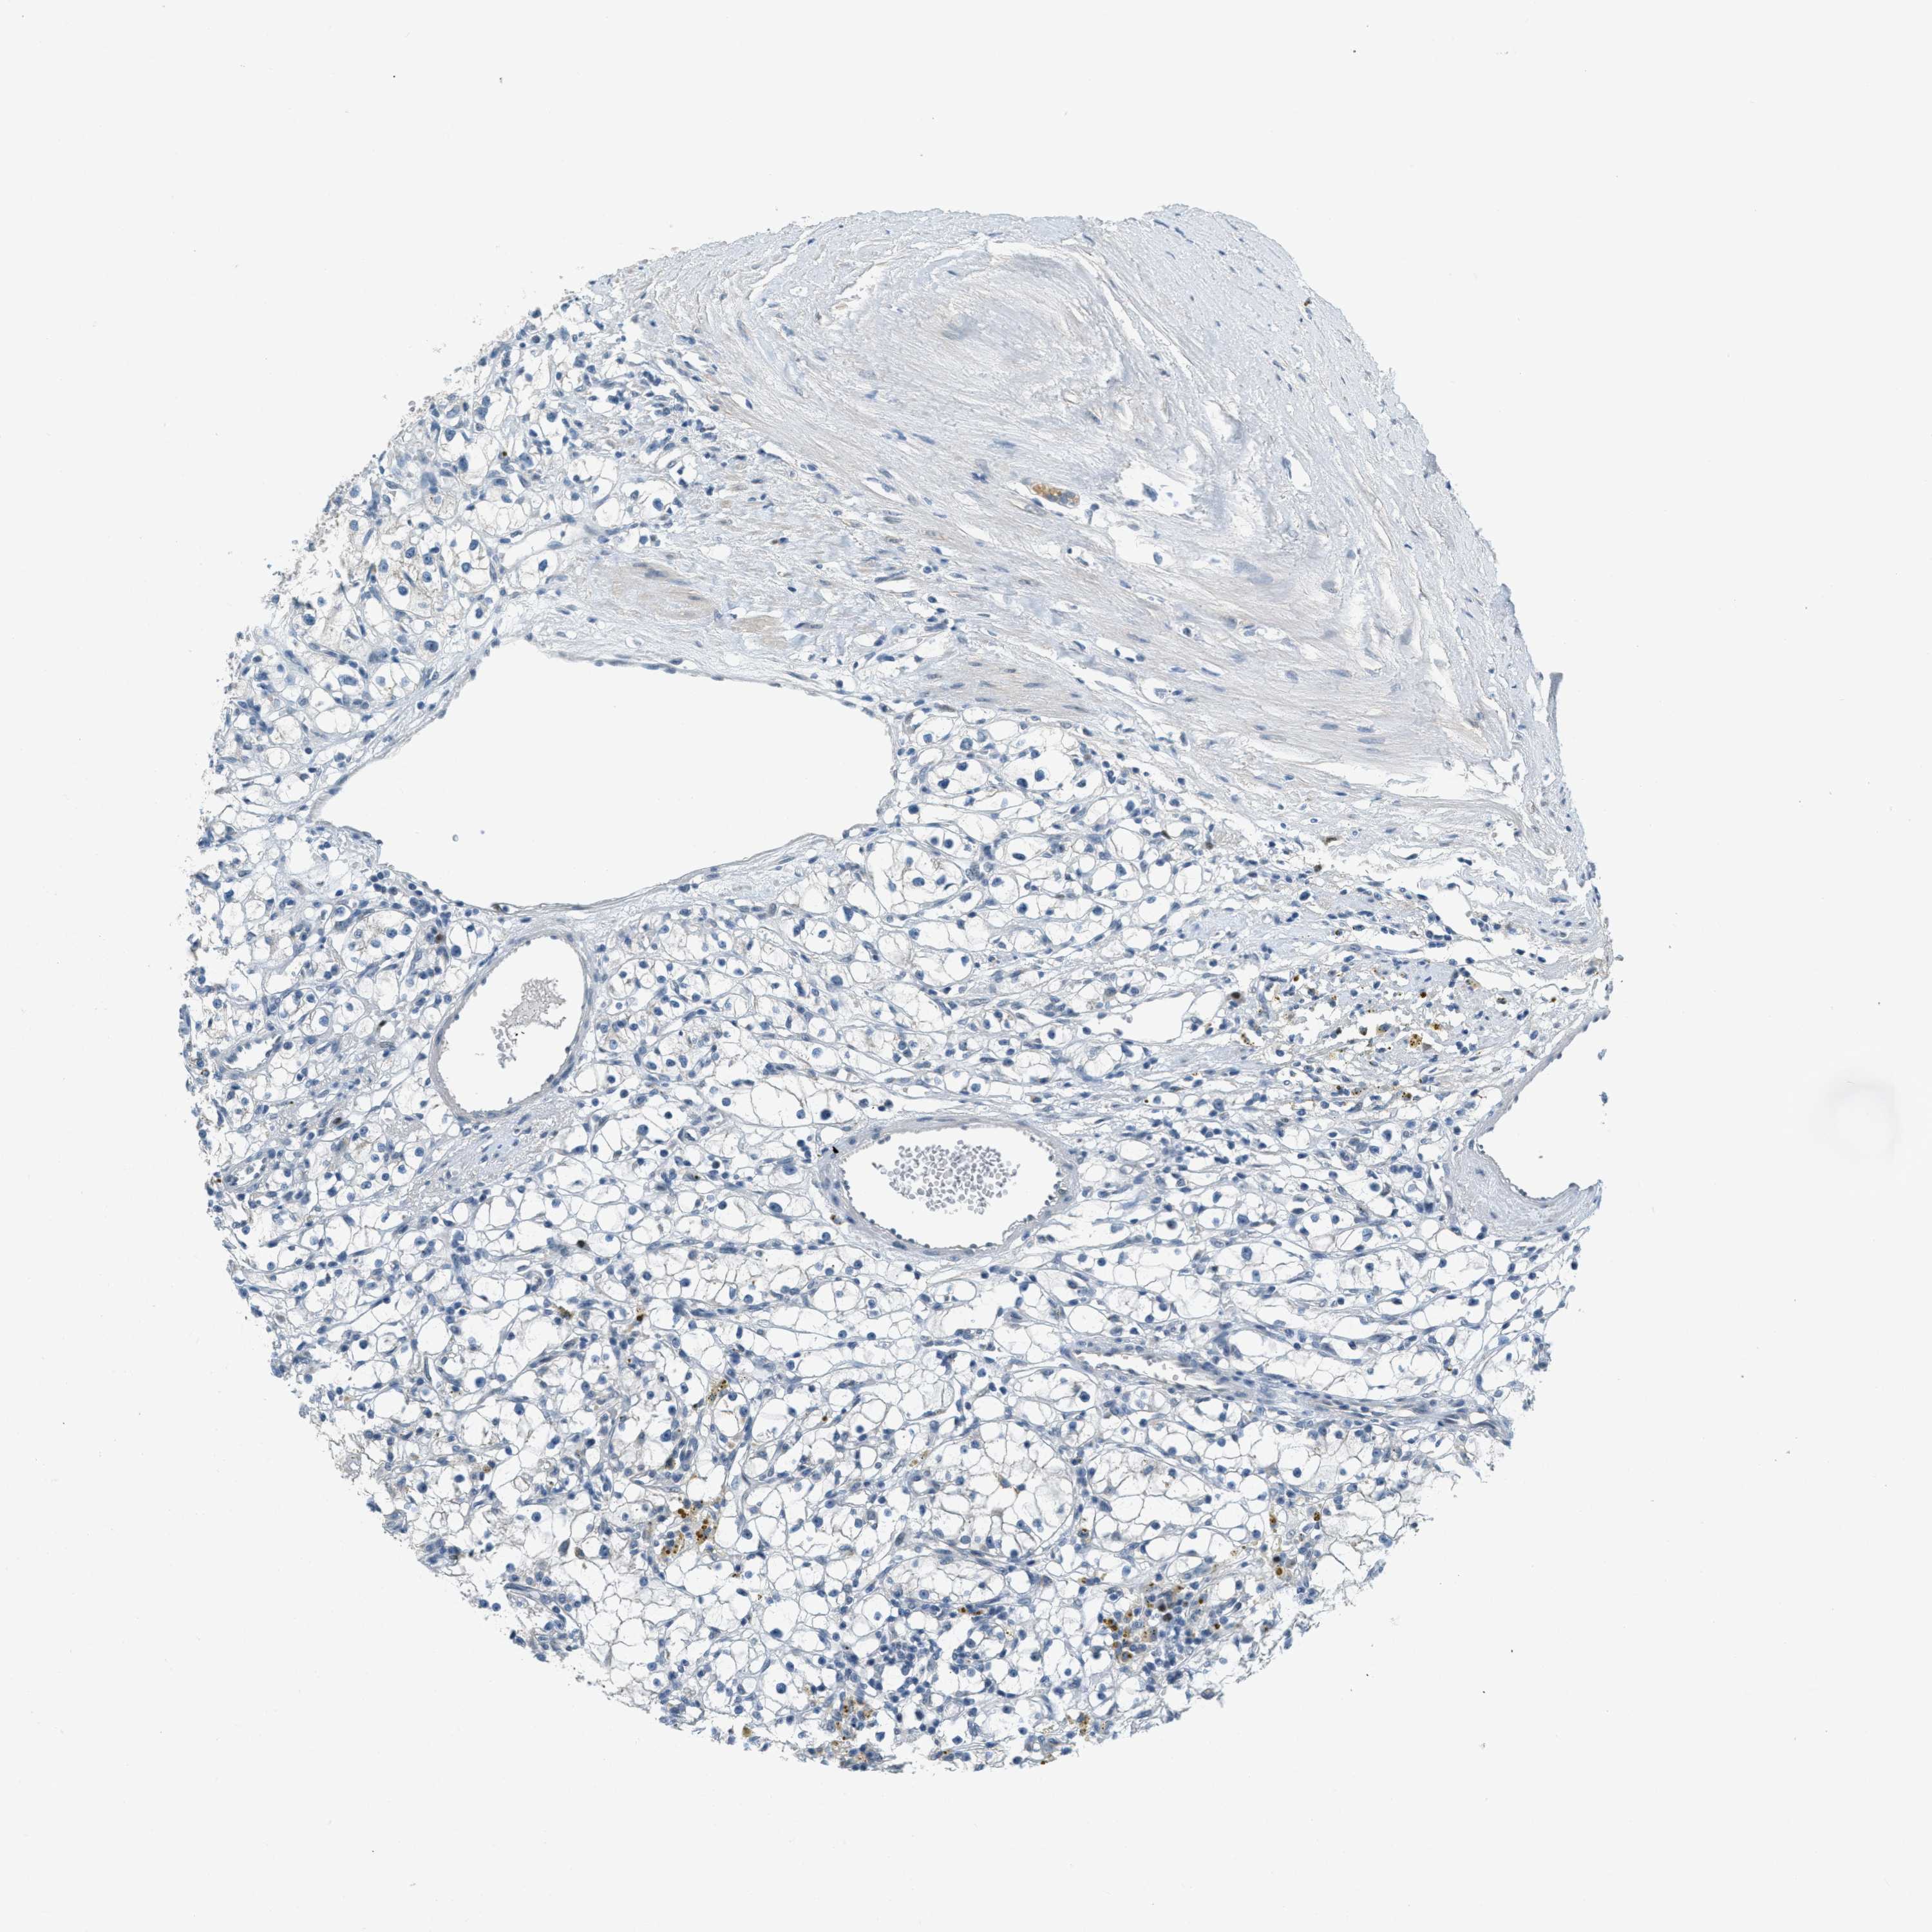

KIDNEY RENAL CLEAR CELL CARCINOMA (VALIDATION) - Interactive survival scatter ploti

The Survival Scatter plot shows the clinical status (i.e. dead or alive) for all individuals in the patient cohort, based on the same data that underlies the corresponding Kaplan-Meier plots. Patients that are alive at last time for follow-up are shown in blue and patients who have died during the study are shown in red.

The x-axis shows the expression levels (FPKM) of the investigated gene in the tumor tissue at the time of diagnosis. The y-axis shows the follow-up time after diagnosis (years). Both axes are complimented with kernel density curves demonstrating the data density over the axes. The top density plot shows the expression levels (FPKM) distribution among dead (red) and alive patients (blue). The right density plot shows the data density of the survived years of dead patients with high and low expression levels respectively, stratified using the cutoff indicated by the vertical dashed line through the Survival Scatter plot. This cutoff is automatically defined based on the FPKM cutoff that minimizes the p-score. The cutoff can be changed by dragging the vertical line or by entering a cutoff value in the square labeled "Current cut-off".

Under the Survival Scatter plot the p-score landscape (black curve; left axis) is shown together with dead median separation (red curve; right axis). Dead median separation is the difference in median mRNA expression between patients who have died with high and low expression, respectively. It is calculated as follows: median FPKM expression of dead patients with high expression - median FPKM expression of dead patients with low expression. This is intended to aid the user in visually exploring custom cutoffs and the associated p-scores and dead median separation.

Individual patient data is displayed and can be filtered by clicking on one or more of the category buttons on the top of the page. Categories describing expression level and patient information include: high, low, alive, dead, female, male and tumor stages. The scale of the x-axis can be toggled between linear and log-scale by clicking on the "x log" button. Mouse-over function shows TCGA ID, patient information and mRNA expression (FPKM) for each patient.

& Survival analysisi

Kaplan-Meier plots summarize results from analysis of correlation between mRNA expression level and patient survival. Patients were divided based on level of expression into one of the two groups "low" (under cut off) or "high" (over cut off). X-axis shows time for survival (years) and y-axis shows the probability of survival, where 1.0 corresponds to 100 percent.

TCF3 is not prognostic in Kidney Renal Clear Cell Carcinoma (validation)

Best expression cut offi

Based on the FPKM value of each gene, patients were classified into two groups and association between prognosis (survival) and gene expression (FPKM) was examined. The best expression cut-off refers the FPKM value that yields maximal difference with regard to survival between the two groups at the lowest log-rank P-value. Best expression cut-off was selected based on survival analysis .

When clicking on this number, the vertical dashed line indicating cut-off, the interactive survival plot, and the Kaplan-Meier curve will be adjusted to show results based on the best expression cut-off.

: 36.42

Median expressioni

Median expression refers to the median FPKM value calculated based on the gene expression (FPKM) data from all patients in this dataset. When clicking on this number, the vertical dashed line indicating cut-off, the interactive survival plot, and the Kaplan-Meier curve will be adjusted to show results based on the median expression.

: N/A

Median follow up timei

Median follow up time refers to the median time (years) after diagnosis with this type of cancer, based on clinical data from all patients in this dataset.

P scorei

Log-rank P value for Kaplan-Meier plot showing results from analysis of correlation between mRNA expression level and patient survival.

N/A

5-year survival highi

5-year survival for patients with higher expression than the expression cutoff.

For melanoma and glioma, 3-year survival is shown.

5-year survival lowi

5-year survival for patients with lower expression than the expression cutoff.

TCGA RNA samplesi

RNA-seq data is reported as average FPKM (number Fragments Per Kilobase of exon per Million reads), generated by the The Cancer Genome Atlas (TCGA) .

Normal distribution across the dataset is visualized with box plots, shown as median and 25th and 75th percentiles. Points are displayed as outliers if they are above or below 1.5 times the interquartile range. FPKM values of the individual samples are presented next to the box plot.

Average pTPM 32.0

Number of samples 100